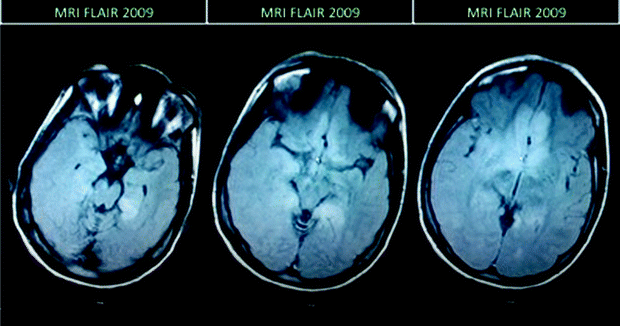

T2/FLAIR MRI showing extensive abnormalities of the bilateral parasagittal frontal lobes and right insula and temporal lobe

There were no changes following gadolinium administration, and there was a normal appearance of the circle of Willis with magnetic resonance angiography.

Follow-up MRI after 2 year interval. FLAIR sequences show evolution of the lesion with loss of parenchyma in the right temporal and insular areas